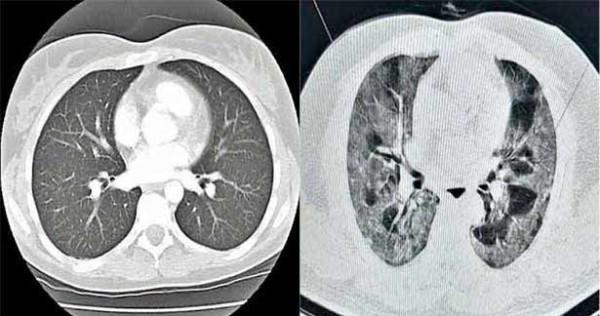

கொரோனாவால் தழும்பு ஏற்பட்டுள்ள நுரையீரல். பாதிப்பு இல்லாத முழுமையாக கருப்பு நிறத்திலான நுரையீரல்.

அவர்களுக்கு கொரோனா வைரஸ் உடலில் இல்லாமல் இருந்தாலும் அதனால் ஏற்பட்ட நுரையீரல் பாதிப்பு காரணமாக இந்த சுவாசபிரச்சினைகள் ஏற்படுவது கண்டறியப்பட்டுள்ளது. சாதாரணமாக கருப்பு நிறத்தில் காணப்படும் நுரையீரல், இந்த தழும்பு ஏற்பட்டால் பாதிக்கப்பட்ட பகுதி கருப்பு நிறம் மாறி வெளிர் வெண்மை நிறமாக மாறிவிடும். சி.டி. ஸ்கேன் பரிசோதனையின் மூலம் இதனை கண்டறிய முடியும். எனவே, அனைவரும் உரிய நேரத்தில் அறிகுறி தென்படும் போதே கொரோனா பரிசோதனை செய்து, வைரசின் தீவிரத்தை ஆரம்ப கட்டத்திலேயே குறைத்து, நுரையீரலில் தழும்புகள் அதிகம் ஏற்படாமல் தற்காத்து கொள்ள வேண்டும்.